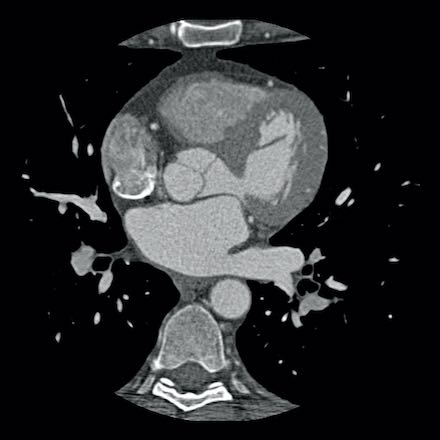

case 2 – CAD-RADS 5/P2/S

First, scroll through the CTA images.

How would you describe the findings on the coronary CTA?

The findings are:

- Stent in the mid

LAD with low-attenuation within the stent suggestive of minimal in-stent

restenosis (<25%). Non-calcified plaque distal to the stent

causing mild stenosis (25-49%). Notice bridging on a short segment in

the distal LAD. - Non-calcified

plaque in the LCX causing mild stenosis (25-49%). - Occlusion of the

proximal OM1 branch with distal filling. - Calcified and

non-calcified plaques in the proximal RCA causing mild (25-49%) stenosis. - Total plaque burden

is moderate based on SIS (four segments including proximal RCA, mid LAD, prox

LCX and OM1).

Due to the occlusion of OM1 branch and presence of the stent, this case

reads as CAD-RADS 5/P2/S, which means that this patient needs further

diagnostic workup.